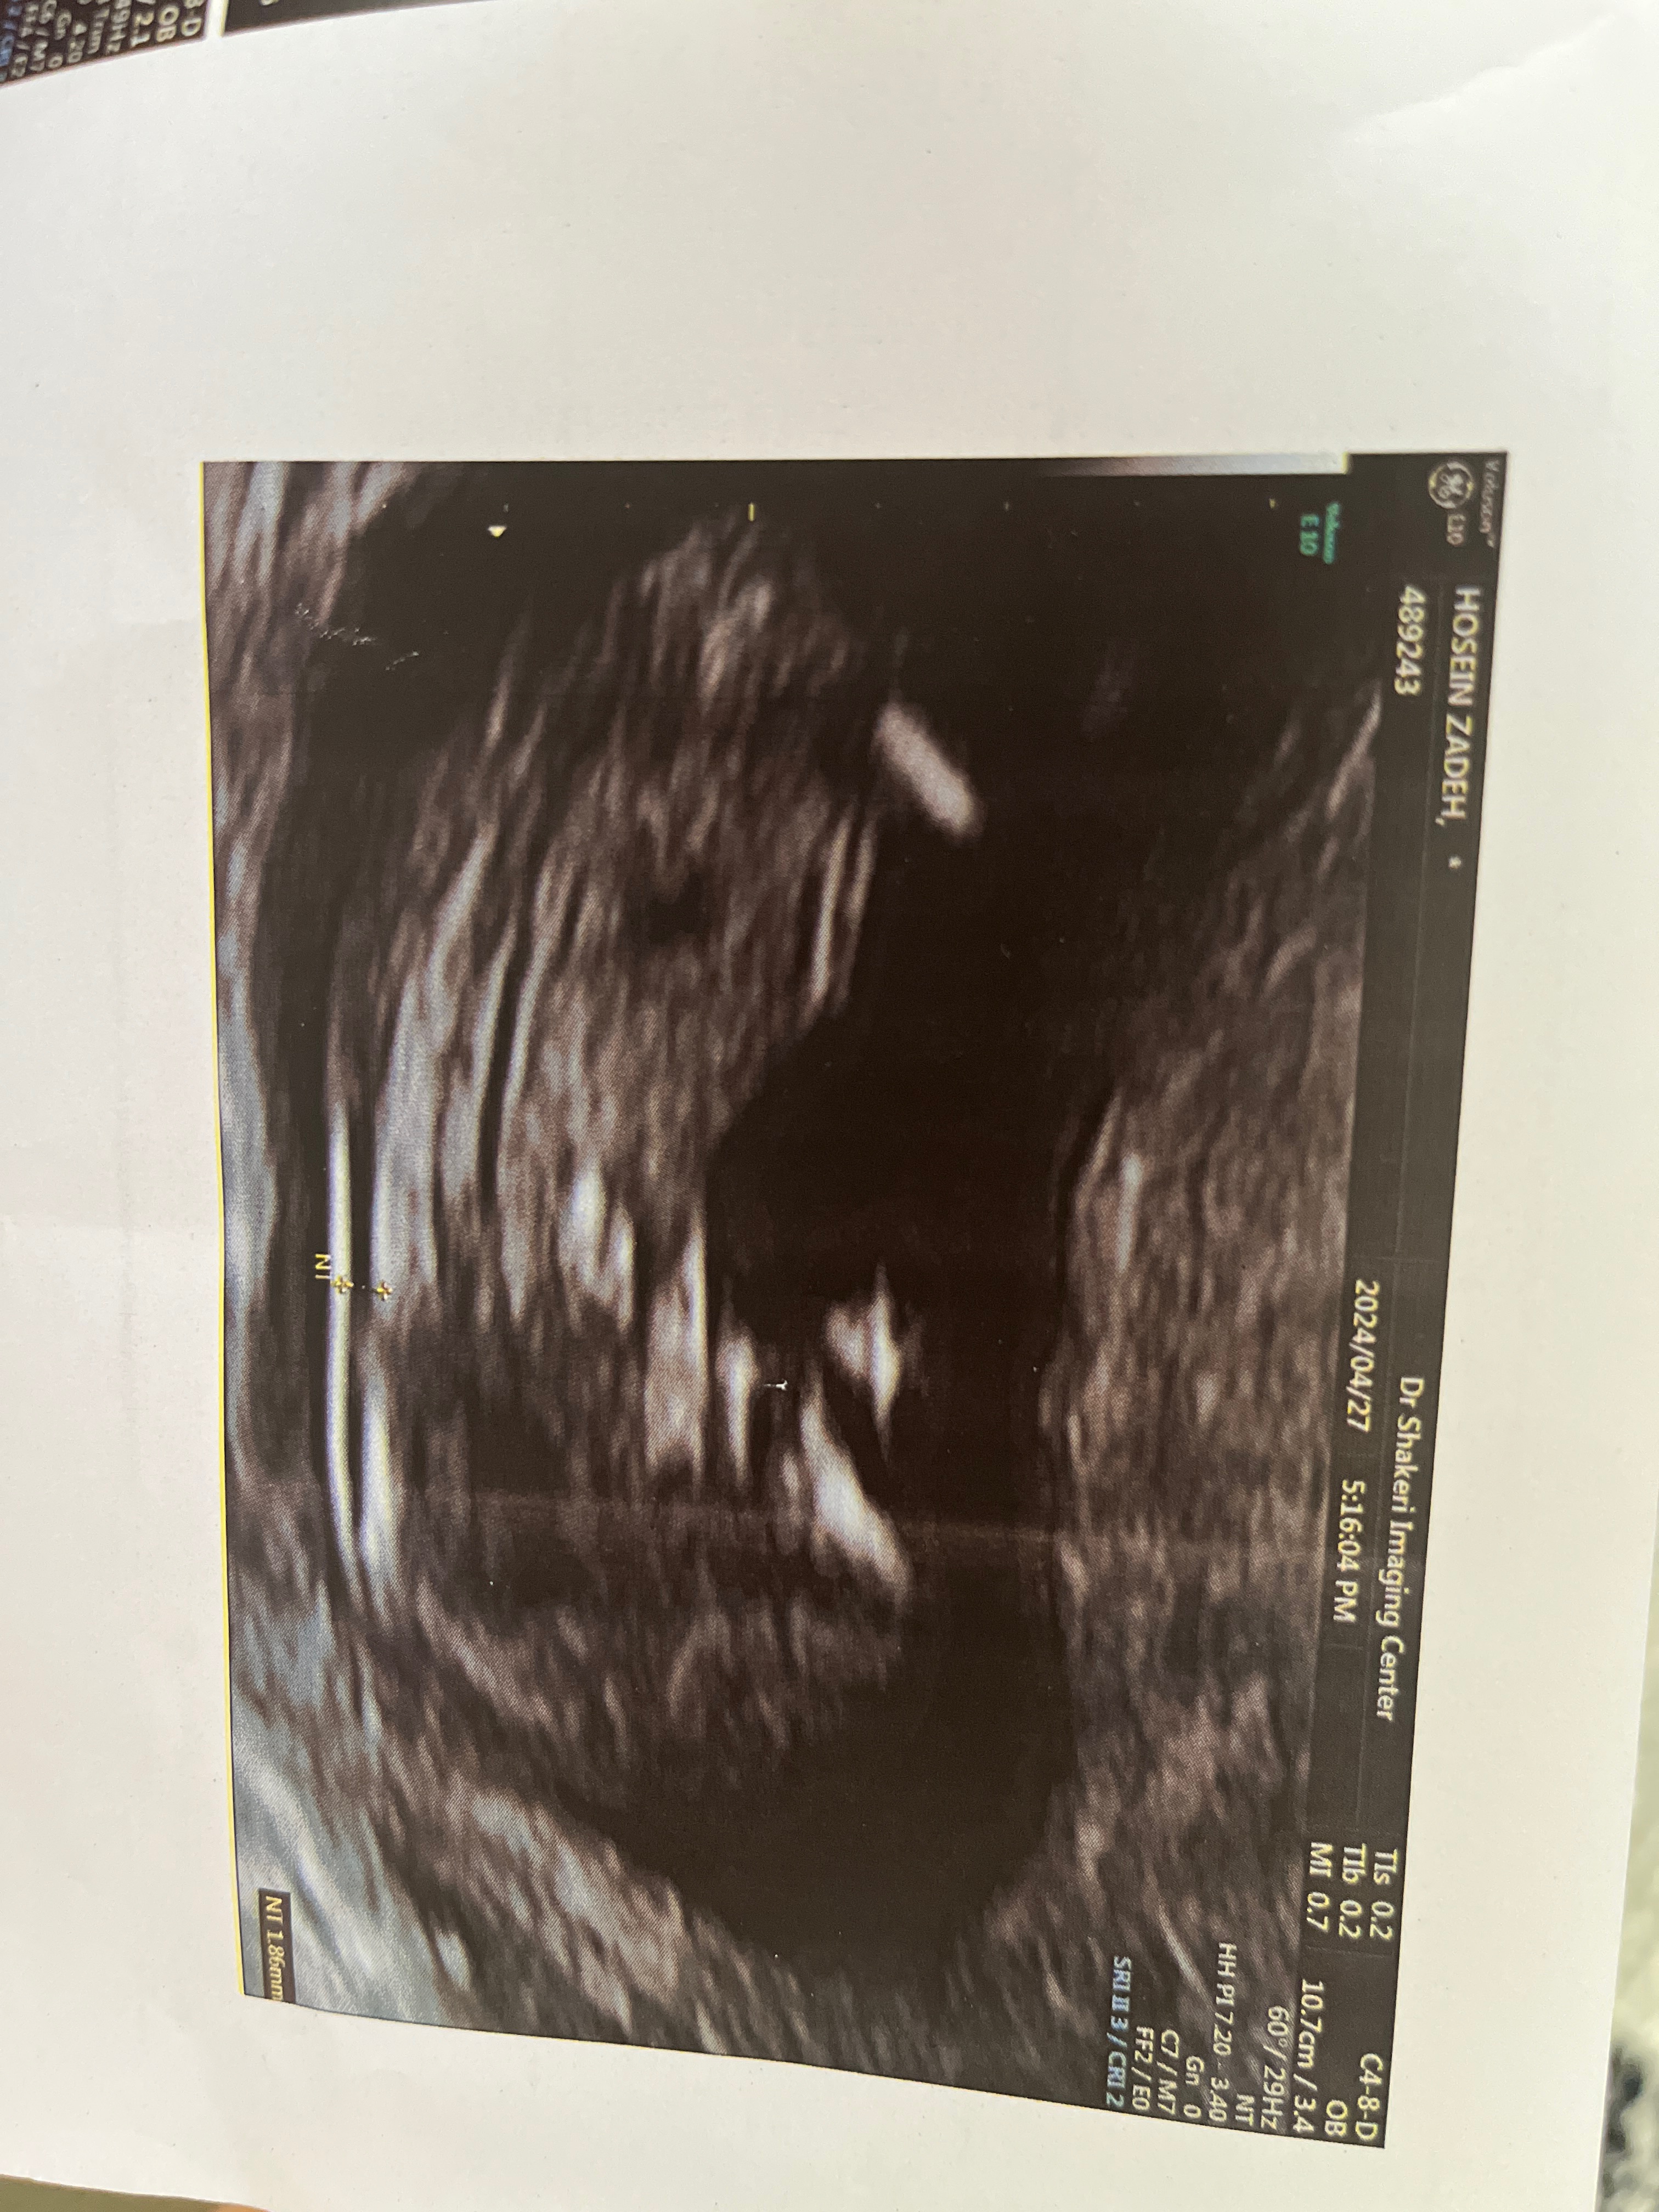

تیکر اومدن شازده پسرمون🙈برای سلامتی نی نیم صلوات بفرستین مرسی❤1398/1/31شب نیمه شعبانفهمیدم که شدی یه تیکهازوجودم👼